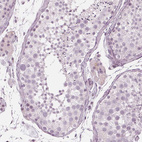

Immunohistochemistry analysis in human endometrium and prostate tissues using HPA029473 antibody. Corresponding PAEP RNA-seq data are presented for the same tissues.